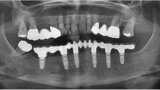

Fig. 15: Panoramic radiograph at delivery of the final CAD/CAM FDP.